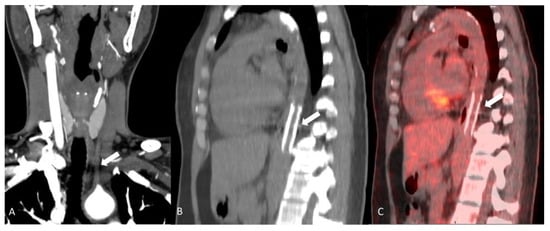

2.1.1. Giant Cell Arteritis

2.1.2. Takayasu’s Arteritis

2.1.3. Clinically Isolated Aortitis (Idiopathic Aortitis)